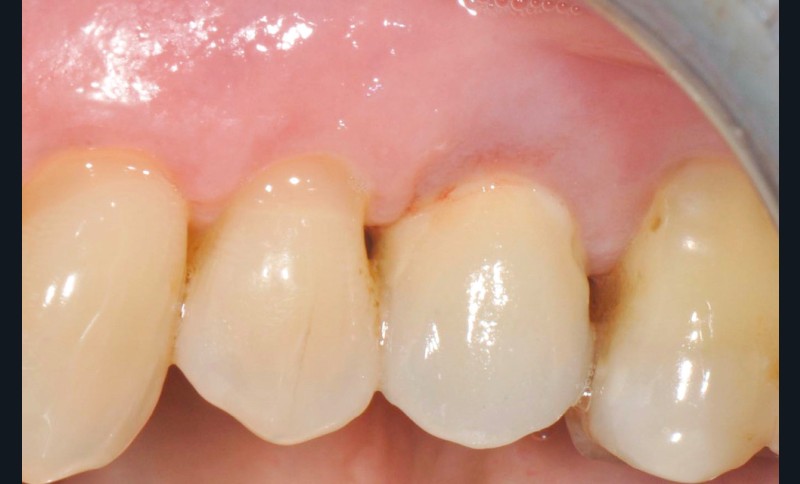

13 et 14. À 3 ans, une régénération osseuse satisfaisante et un bel aspect des tissus péri-implantaires sont observés. Les poches font 3 mm en mésial, distal et palatin, et 2 mm en vestibulaire. Il n’y a pas de saignement au sondage.